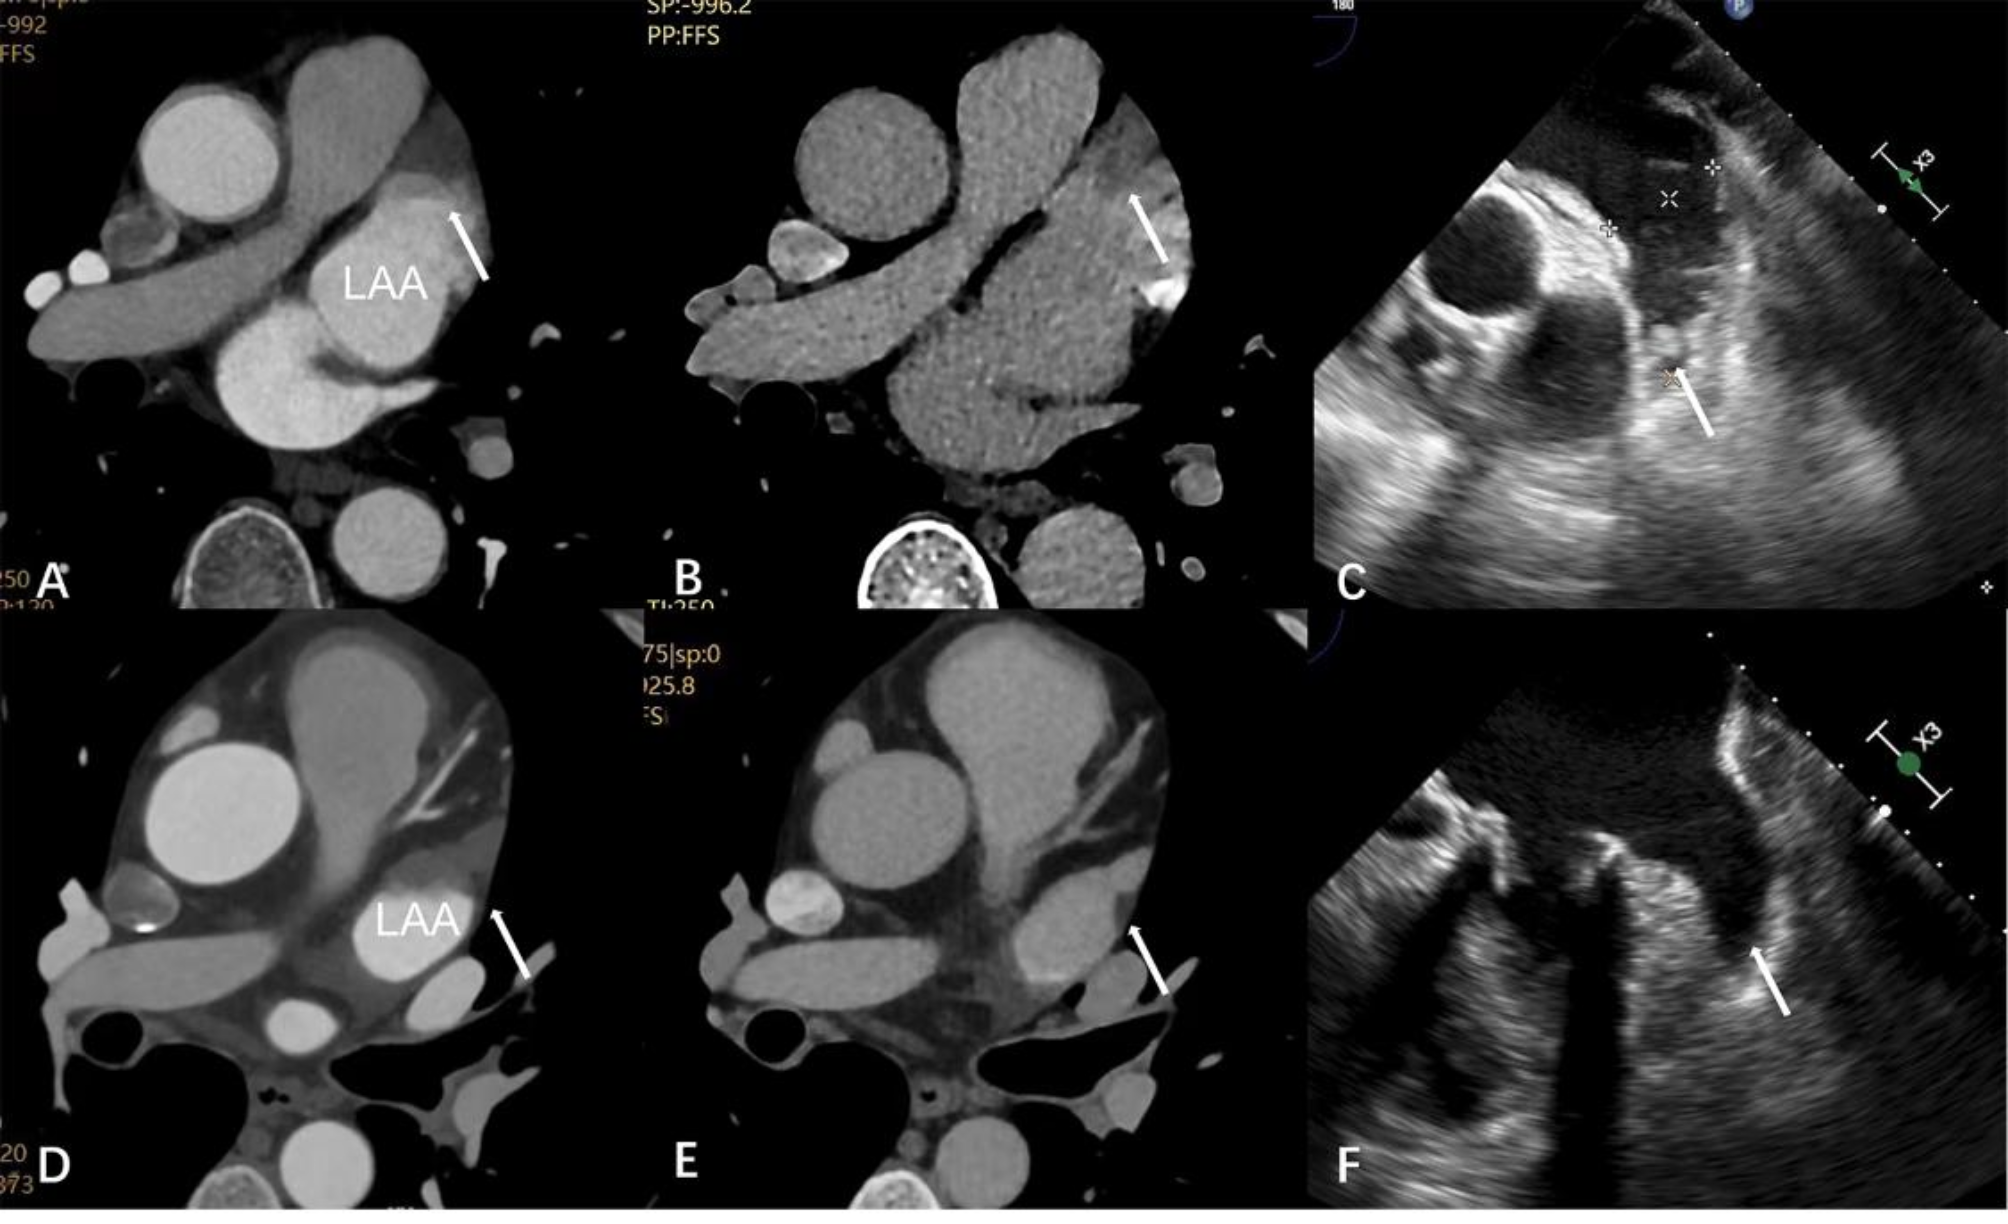

Fig. 3

Left atrial appendage thrombus and pseudo-thrombus. There was a filling defect in the LAA (arrow) in the early phase (A) which persisted in the delayed scan (B) and was confirmed on the TEE (C) (arrow). There was a filling defect in the LAA (arrow) in the early phase (D) which persisted in the delayed scan (E) and was not detected on the TEE (F) (arrow). LAA Left atrial appendage. TEE transesophageal echocardiogram.